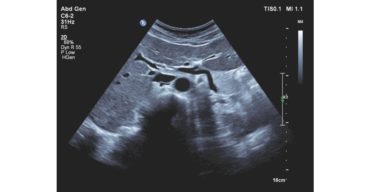

ecografo PHILIPS affiniti 30

La scelta di un nuovo sistema ecografico è tutta questione di equilibrio. Servono velocemente informazioni diagnostiche precise, un'interfaccia utente semplificata ma intuitiva e facilità di accesso alle funzioni cruciali, unitamente a un design ergonomico e alla tecnologia più recente.

Affiniti 30 rappresenta un’investimento intelligente in quanto risponde compiutamente alle sollecitazioni quotidiane legate alla produttività, alla qualità diagnostica e ai bassi costi di gestione.